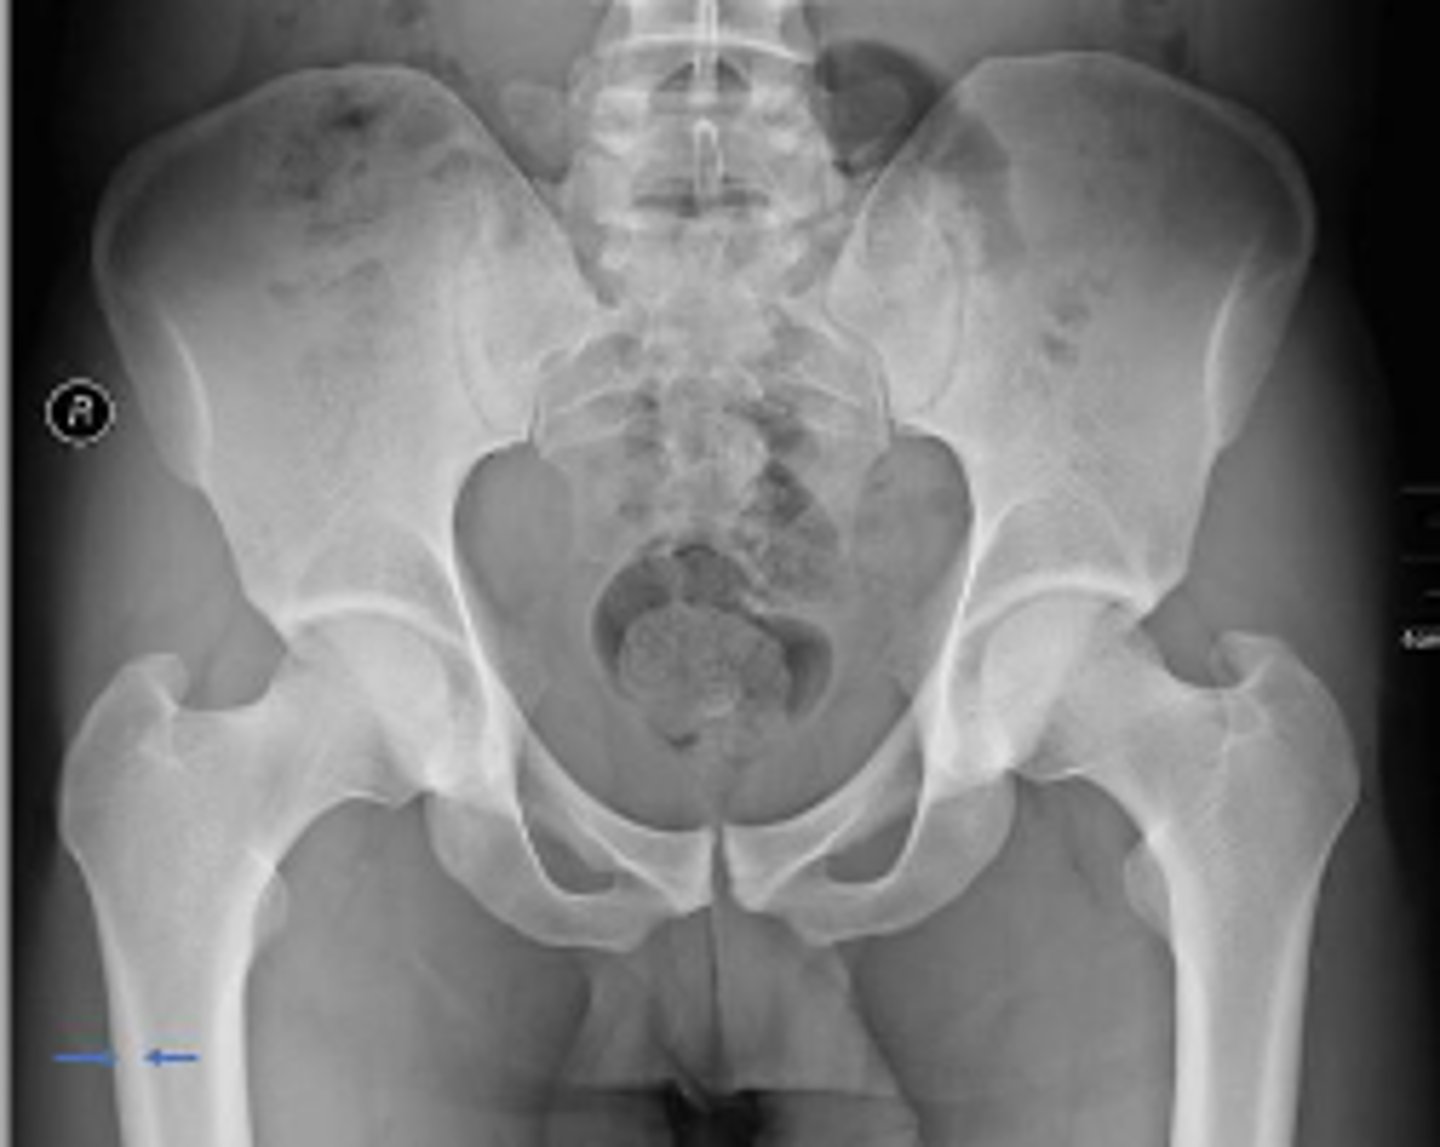

Posterior hip dislocation

What is most significant radiographic finding?

Shenton's line

What is the name of the assessment?

From the undersurface of the femoral neck

continued to the inferior aspect of the superior

pubic ramus

What are the osseous land marks for this assessment?

Hip dislocation, fracture

Name 2 conditions that may result in an abnormal assessment?